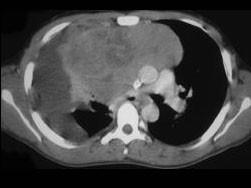

女,34岁,咳嗽,咯血半月余,请结合影像学检查,选出最可能的诊断 ( )A、神经源性肿瘤B、肺癌C、淋巴瘤D、胸腺瘤E、纵隔畸胎瘤

问题 女,34岁,咳嗽,咯血半月余,请结合影像学检查,选出最可能的诊断 ( )

选项 A、神经源性肿瘤 B、肺癌 C、淋巴瘤 D、胸腺瘤 E、纵隔畸胎瘤

答案 E